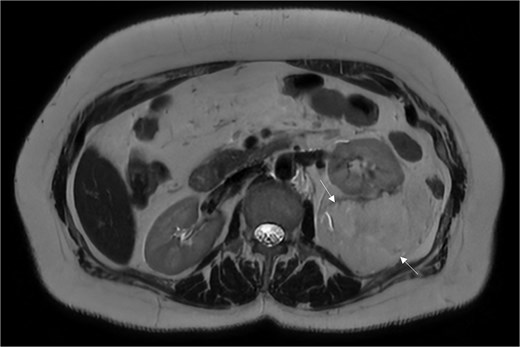

A 54-year-old non-smoker, post-menopausal female, presented to the outpatient clinic with vague abdominal pain (score of 4/10) radiating to the back. Her past medical history included hypertension, diabetes, hypercholesterolemia, and laparoscopic myomectomy for a uterine polyp. No family history of cancer reported. Her abdominal exam revealed a soft, non-tender abdomen with no signs of organomegaly. Blood test results showed C-reactive protein – 55.3 mg/L, creatinine – 53.3 μmol/L, normal basic metabolic panel, procalcitonin – 0.06 ng/mL, Hb – 9.3 g/dL. A computed tomography (CT) scan of abdomen and pelvis (Fig. 1) with contrast revealed a large heterogeneous retroperitoneal mass (12 × 7.5 × 8.2 cm), fat predominant, and suspicious for liposarcoma. A magnetic resonance imaging (MRI) of the abdomen (Fig. 2) was ordered to further delineate the soft tissue mass, which showed a large mass in the left posterior pararenal space measuring 15 × 9.2 × 7.7 cm. The left kidney, splenic artery, and vein appeared to be anteriorly displaced by the mass. This mass effect was also identified on the distal body and tail of pancreas. Tumor markers were ordered as mass appeared suspicious on imaging – CA-125, CA 15–3, CA 19–9, and carcinoembryonic antigen; all reported as normal. A multidisciplinary meeting was planned with provisional diagnosis of renal liposarcoma, and decision was made to opt for surgical excision. Patient underwent exploratory laparotomy with retroperitoneal mass excision and partial left nephrectomy. Her hospital stay was uneventful, and she was discharged after 5 days with full recovery. On histopathology (Fig. 3), the specimen demonstrated a classic fat-predominant benign renal PEComa (Angiomyolipoma or AML). Immunohistochemical stains indicated strong cytoplasmic positivity for HMB-45, smooth muscle actin (SMA), Cathepsin-K, and Melan-A, while negative for PAX-8, SF-1, and MDM 2. Atypical histological features, such as nuclear pleomorphism, increased mitotic activity, or coagulative necrosis, were not observed, ruling out a malignant variant.

An MRI of the abdomen depicting a large mass in the left posterior pararenal space.